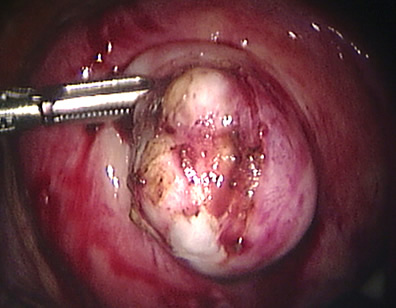

Intraoperative photos

The uterus is opened and the fibroid has become visible.

The fibroid has been removed completely from the uterus and it is shown free in the abdominal cavity.